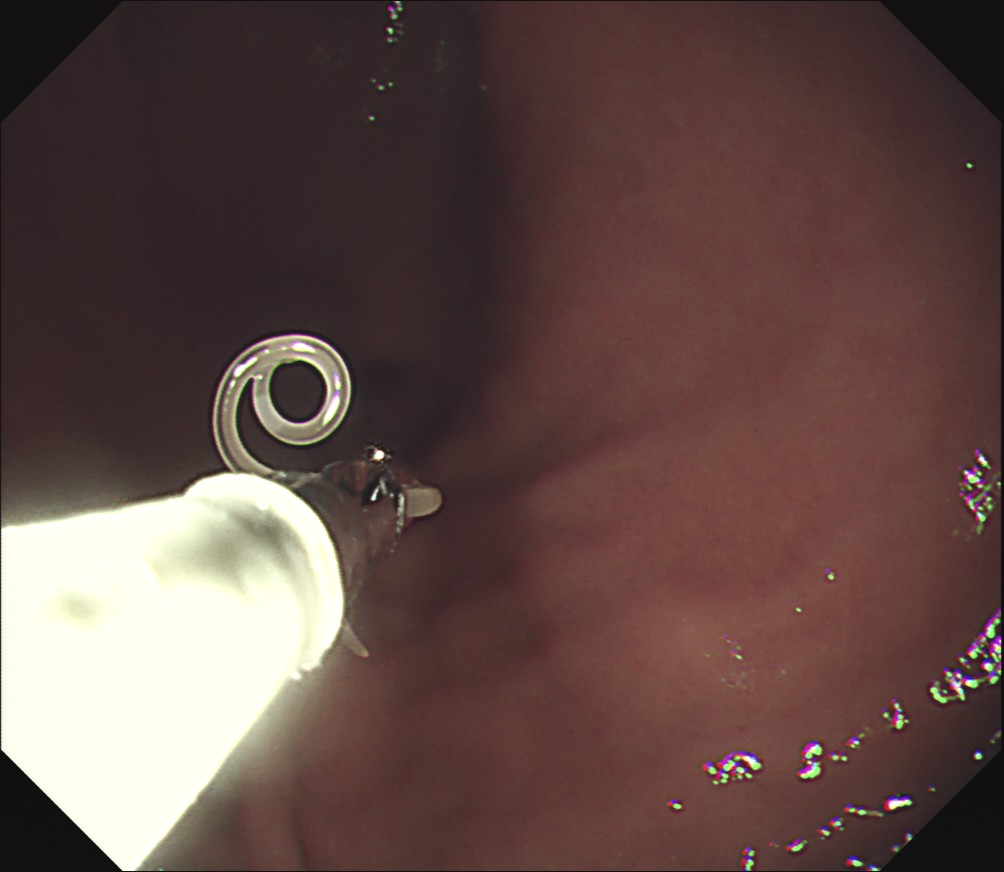

これですね。

少し透明感のある細長い虫体で、

頭部は粘膜にかみこんでいます。

鉗子で虫体をつかみゆっくりと引っ張ります。

強く引っ張ると途中で切れて、

頭部が粘膜に残ってしまいます。

綱引きのような形なりますが、

ここまで来ると勝ちですので、

慎重にゆっくりと引き抜きます。

捕獲に成功しました!

カメラから鉗子を引き抜いて摘出完了です。

噛みついていた場所から少量の出血がありますが、

周囲の粘膜はほとんど腫れていません。

通常はもっと赤くなって蕁麻疹のようにむくんでいます。

今回の症例がそれほど痛みが強くなかったのは、

粘膜の炎症の波及が軽かったためと思われます。